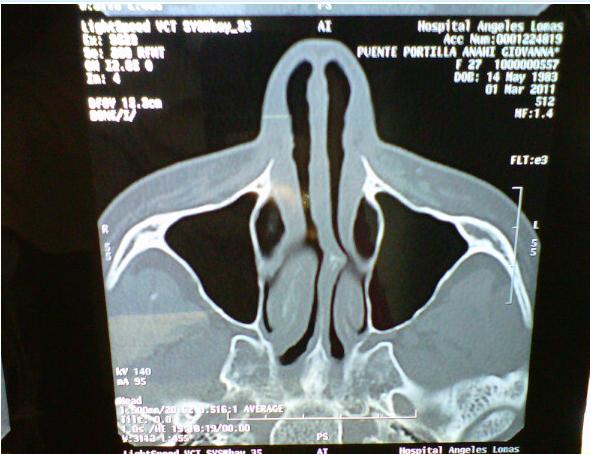

Ao saber desta notícia, Anahí logo postou em seu Twitter, uma foto do raio-x de seu rosto, provando que a cirurgia, foi sim necessária por causa do desvio.